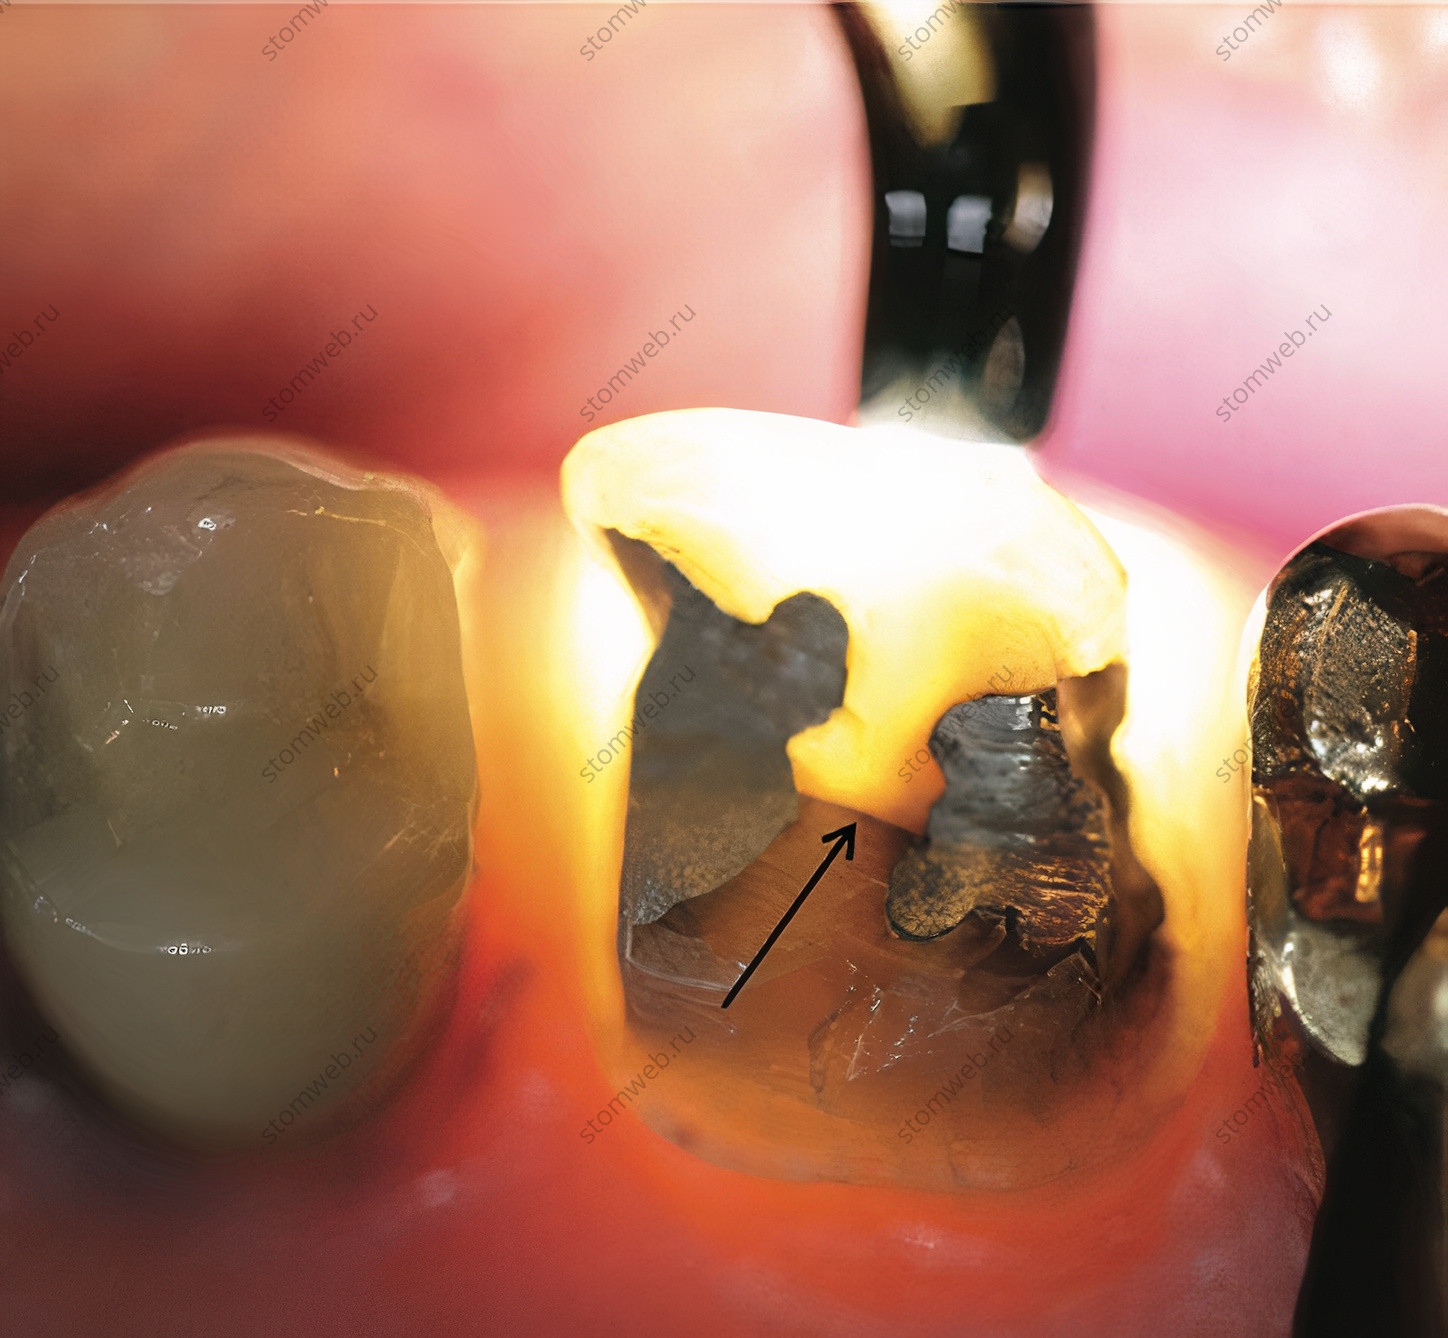

При визуальном осмотре можно обнаружить разные признаки трещины, особенно при помощи трансиллюминации (рис. 13) и красителей, таких как метиленовый синий или красный краситель (рис. 12). Возможность использования трансиллюминации зависит от того, есть ли реставрация на зубе, так как луч света должен пройти через зуб; если есть трещина, свет преломляется и не проходит напрямую, так что противоположная поверхность зуба будет темной. Вдобавок, микроскоп также может быть очень ценным помощником в поиске трещин, но одно только увеличение не стоит использовать как самостоятельный способ поиска трещин. В сочетании с нанесением красителя трещины станут видимыми.

Рисунок 13. Пример мезиодистальной трещины (указано стрелкой) в верхнечелюстном моляре, отпрепарированном под коронку, обнаруженной с помощью трансиллюминации